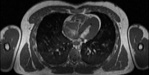

Visible Human male: Sectio transversalis 1454

CT

NMR

Pd                          / T2 \                         T1